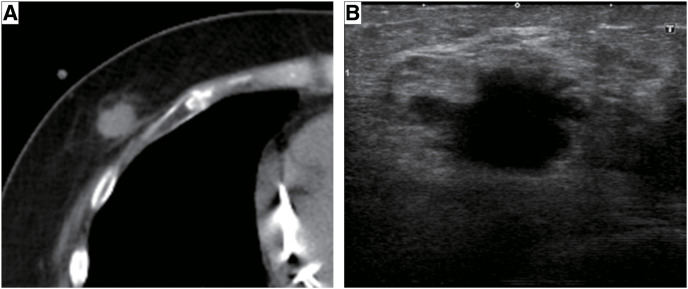

Case presentation: A 64-year-old female with a history of DC and sustained ventricular tachycardia, who had received cardiac resynchronization therapy with defibrillator implantation, underwent breast cancer surgery. She had been repeatedly hospitalized for heart failure with an LVEF of 19% and New York Heart Association (NYHA) Class III status, and heart transplant surgery was considered. However, a screening computed tomography scan revealed right breast cancer, and neither heart transplantation nor breast cancer surgery was performed. Endocrine therapy was initiated and failed 48 months after administration. Although the LVEF remained low at 21%, the NYHA classification improved to Class II, and she had not been hospitalized for heart failure for an extended period since her breast cancer diagnosis. Therefore, breast cancer surgery was performed under general anesthesia and no postoperative complications were observed throughout the course of the surgery.